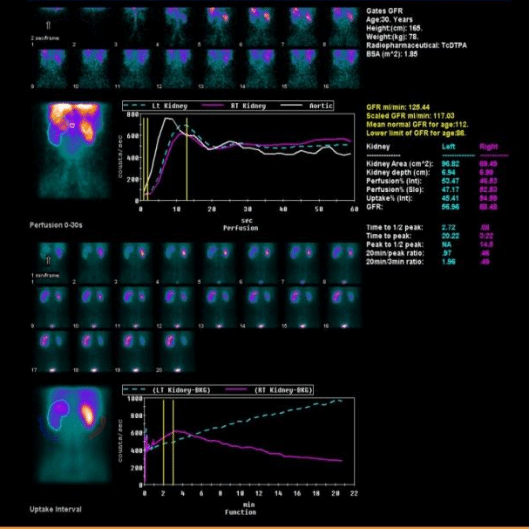

静脉注射经肾小球滤过或肾小管分泌的显像剂后,用核医学成像设备快速动态采集,获得肾脏血流灌注影像、肾实质影像,随后显像剂随尿液流经肾盏、肾盂和输尿管到达膀胱的序列影像,来观察肾脏的位置、大小、形态、功能和上尿路通畅情况,特别是能定量测定分肾功能(左、右肾的各自功能)。

左图,男,30岁,左肾积水,左肾功能大致正常,左上尿路梗阻。